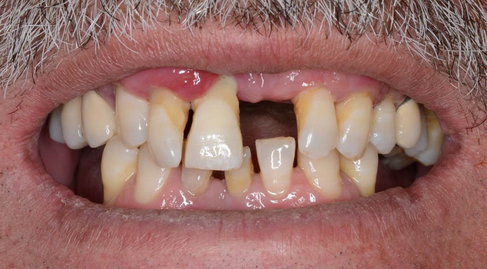

- Initial situation with a high lip position (left), Intra oral view of the area (right)

- Missing tooth on #21

- Periodontal disease